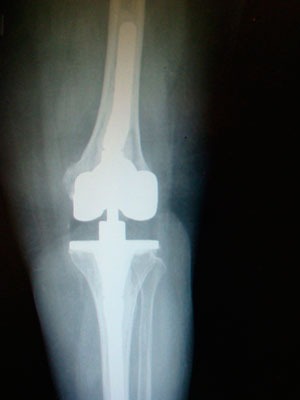

¿Qué hacer si ha fracasado la prótesis de rodilla?

Si la causa es la infección de la prótesis de rodilla, el especialista, con la ayuda de un equipo multidisciplinar, establecerá el mejor tratamiento posible, en un tiempo o en dos tiempos quirúrgicos.

Tanto si la causa es infecciosa como si la causa es la inestabilidad o la pérdida ósea, o el aflojamiento mecánico, no infeccioso, el cirujano buscará restaurar la biomecánica de la articulación, la pérdida de hueso y conseguir colocar una nueva prótesis con una fijación sólida al hueso remanente y que le aporte al paciente una estabilidad inmediata.

Hay diferentes medidas para manejar la pérdida de hueso, como el relleno de cemento (para defectos de hasta 3 mm), el uso de cuñas o aumentos metálicos (hasta un máximo de 15 mm de pérdida de hueso en el fémur distal y 10 mm en la tibia), la utilización de vástagos modulares de extensión (prolongaciones de la prótesis hacía el canal del fémur y de la tibia que consiguen la fijación y reparto de las cargas en una zona más sana), el uso de injerto óseo, o la mejora en la fijación en la metáfisis mediante vainas o conos metafisarios de metal ultraporoso que favorecen la incorporación del injerto óseo y la fijación de la prótesis.

El cirujano ha de buscar la prótesis con menor grado de constricción posible que aporte estabilidad.

En general utilizaremos una prótesis de rodilla tipo bisagra rotatoria en caso de ausencia de ambos ligamentos colaterales, tendencia a la hiperextensión severa, pérdida ósea masiva con ligamentos colaterales insuficientes o no reparables, graves deformidades axiales, o ante una discrepancia severa del espacio articular en flexión y en extensión, que no se puede solucionar mediante aumentos modulares.

Los vástagos cementados presentan como ventajas una mayor versatilidad, con la posibilidad de usarse ante canales deformes, pueden ser más cortos, liberan antibiótico, permiten una fijación inmediata, y los estudios muestran una supervivencia del 94% a los 10 años.

La decisión final dependerá del conocimiento y nivel de experiencia del cirujano, teniendo en cuenta la evidencia científica disponible.

Los vástagos intramedulares cementados permiten repartir las cargas en un área de hueso más grande, evitando el fracaso de las prótesis de revisión. El uso de cemento con 1-2 antibióticos permitirá prevenir nuevas complicaciones, como en las prótesis primarias de rodilla.